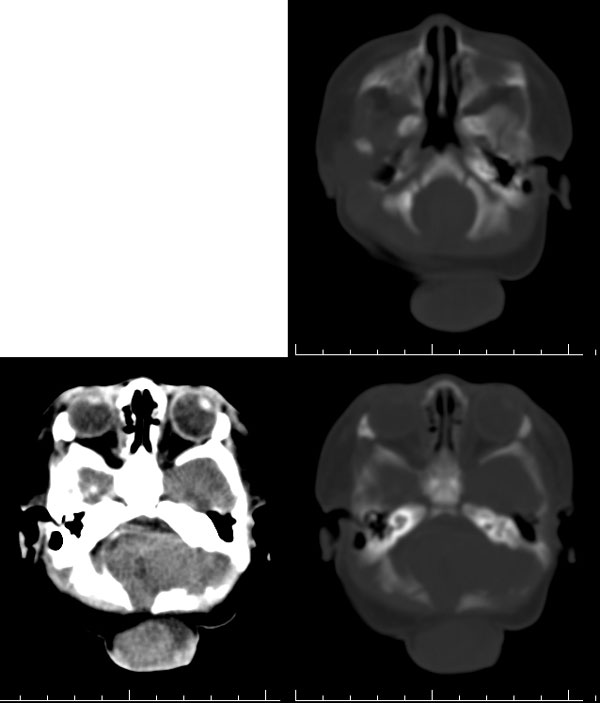

枕骨缺损,脑膜脑膨出。同时第4脑室挤压变形、闭塞,致使第3脑室、双侧侧脑室显著积水、扩张,过高的颅内压推挤脑实质,致使颅骨内板出现多而且深的脑回样压迹,脑细胞水肿,皮质、白质分界不清。

枕骨脑裂畸形伴脑膜脑膨出,双侧脑室扩张积水,第四脑室变窄致使双侧侧脑室及第三脑室积水,

枕骨缺损,脑膜脑膨出。同时第4脑室挤压变形、闭塞,致使第3脑室、双侧侧脑室显著积水、扩张.

意见:1,枕骨闭合不全并脑膜脑膨出;

2,第四脑室发育不全或中脑导水管先天狭窄(或闭锁)并幕上脑室扩张积水.

从图像分析看到的是三、侧脑室的积水,颅骨凹凸不平应是脑压高引起的,脑膜膨出是因脑压增大所致。综合考虑是:中脑水管发育畸形(狭窄或闭锁不全)并三、四脑室积水。枕骨发育不全伴脑脊膜膨出。